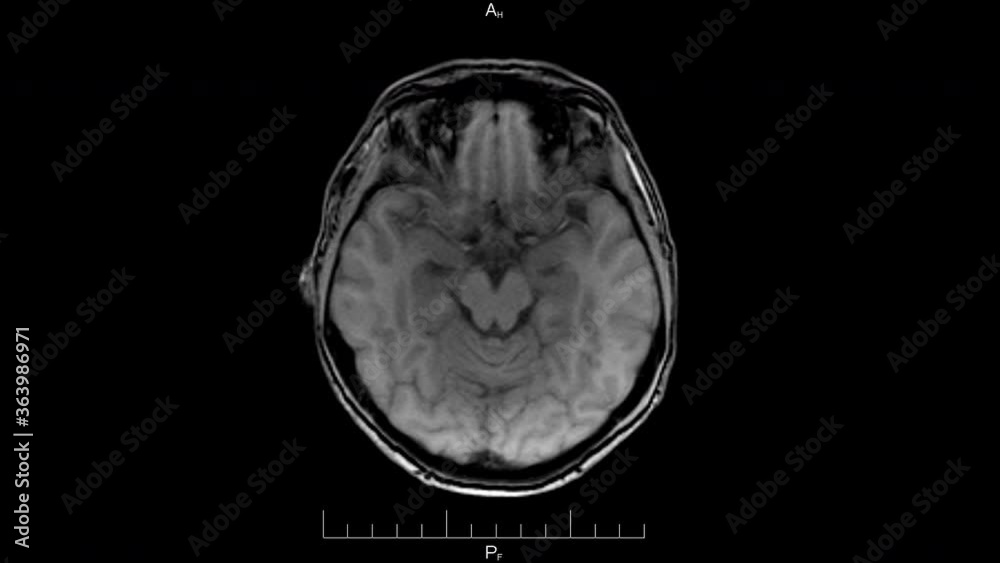

From stock.adobe.com

High resolution resonance image scan of brain epi syndrome Mri Head Dangers The test is generally safe and painless, with little risk for complication, but there are a few elements that may lead to discomfort and distress. Your doctor may also order a head mri to investigate symptoms such as: A head mri can help determine whether you sustained any damage from a stroke or head injury. A brain mri, also called. Mri Head Dangers.